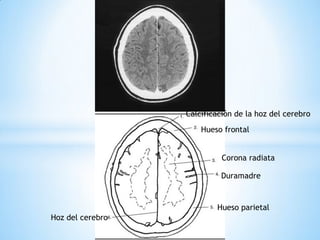

Duramadre

Hoz del cerebro

Calcificación de la hoz del cerebro

Hueso frontal

Hueso parietal

Corona radiata

Hoz del cerebro Corona radiata Hueso frontal Hueso parietal Duramadre Hoz del cerebro

Calcificación de lahoz del cerebro Hueso frontal Hoz del cerebro Hueso parietal Corona radiata Duramadre